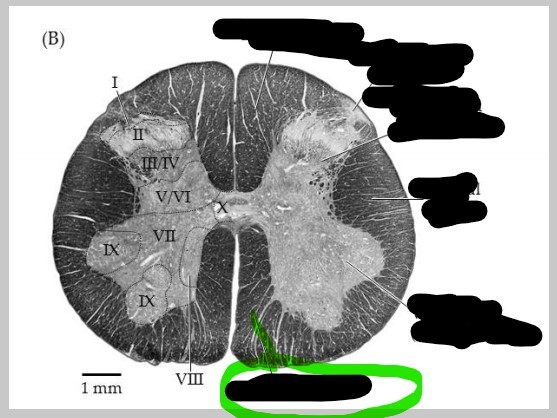

Spinal cord - ventral horn

left and right anterior masses of gray matter; primarily house the cell bodies of somatic motor neurons which innervate skeletal muscle